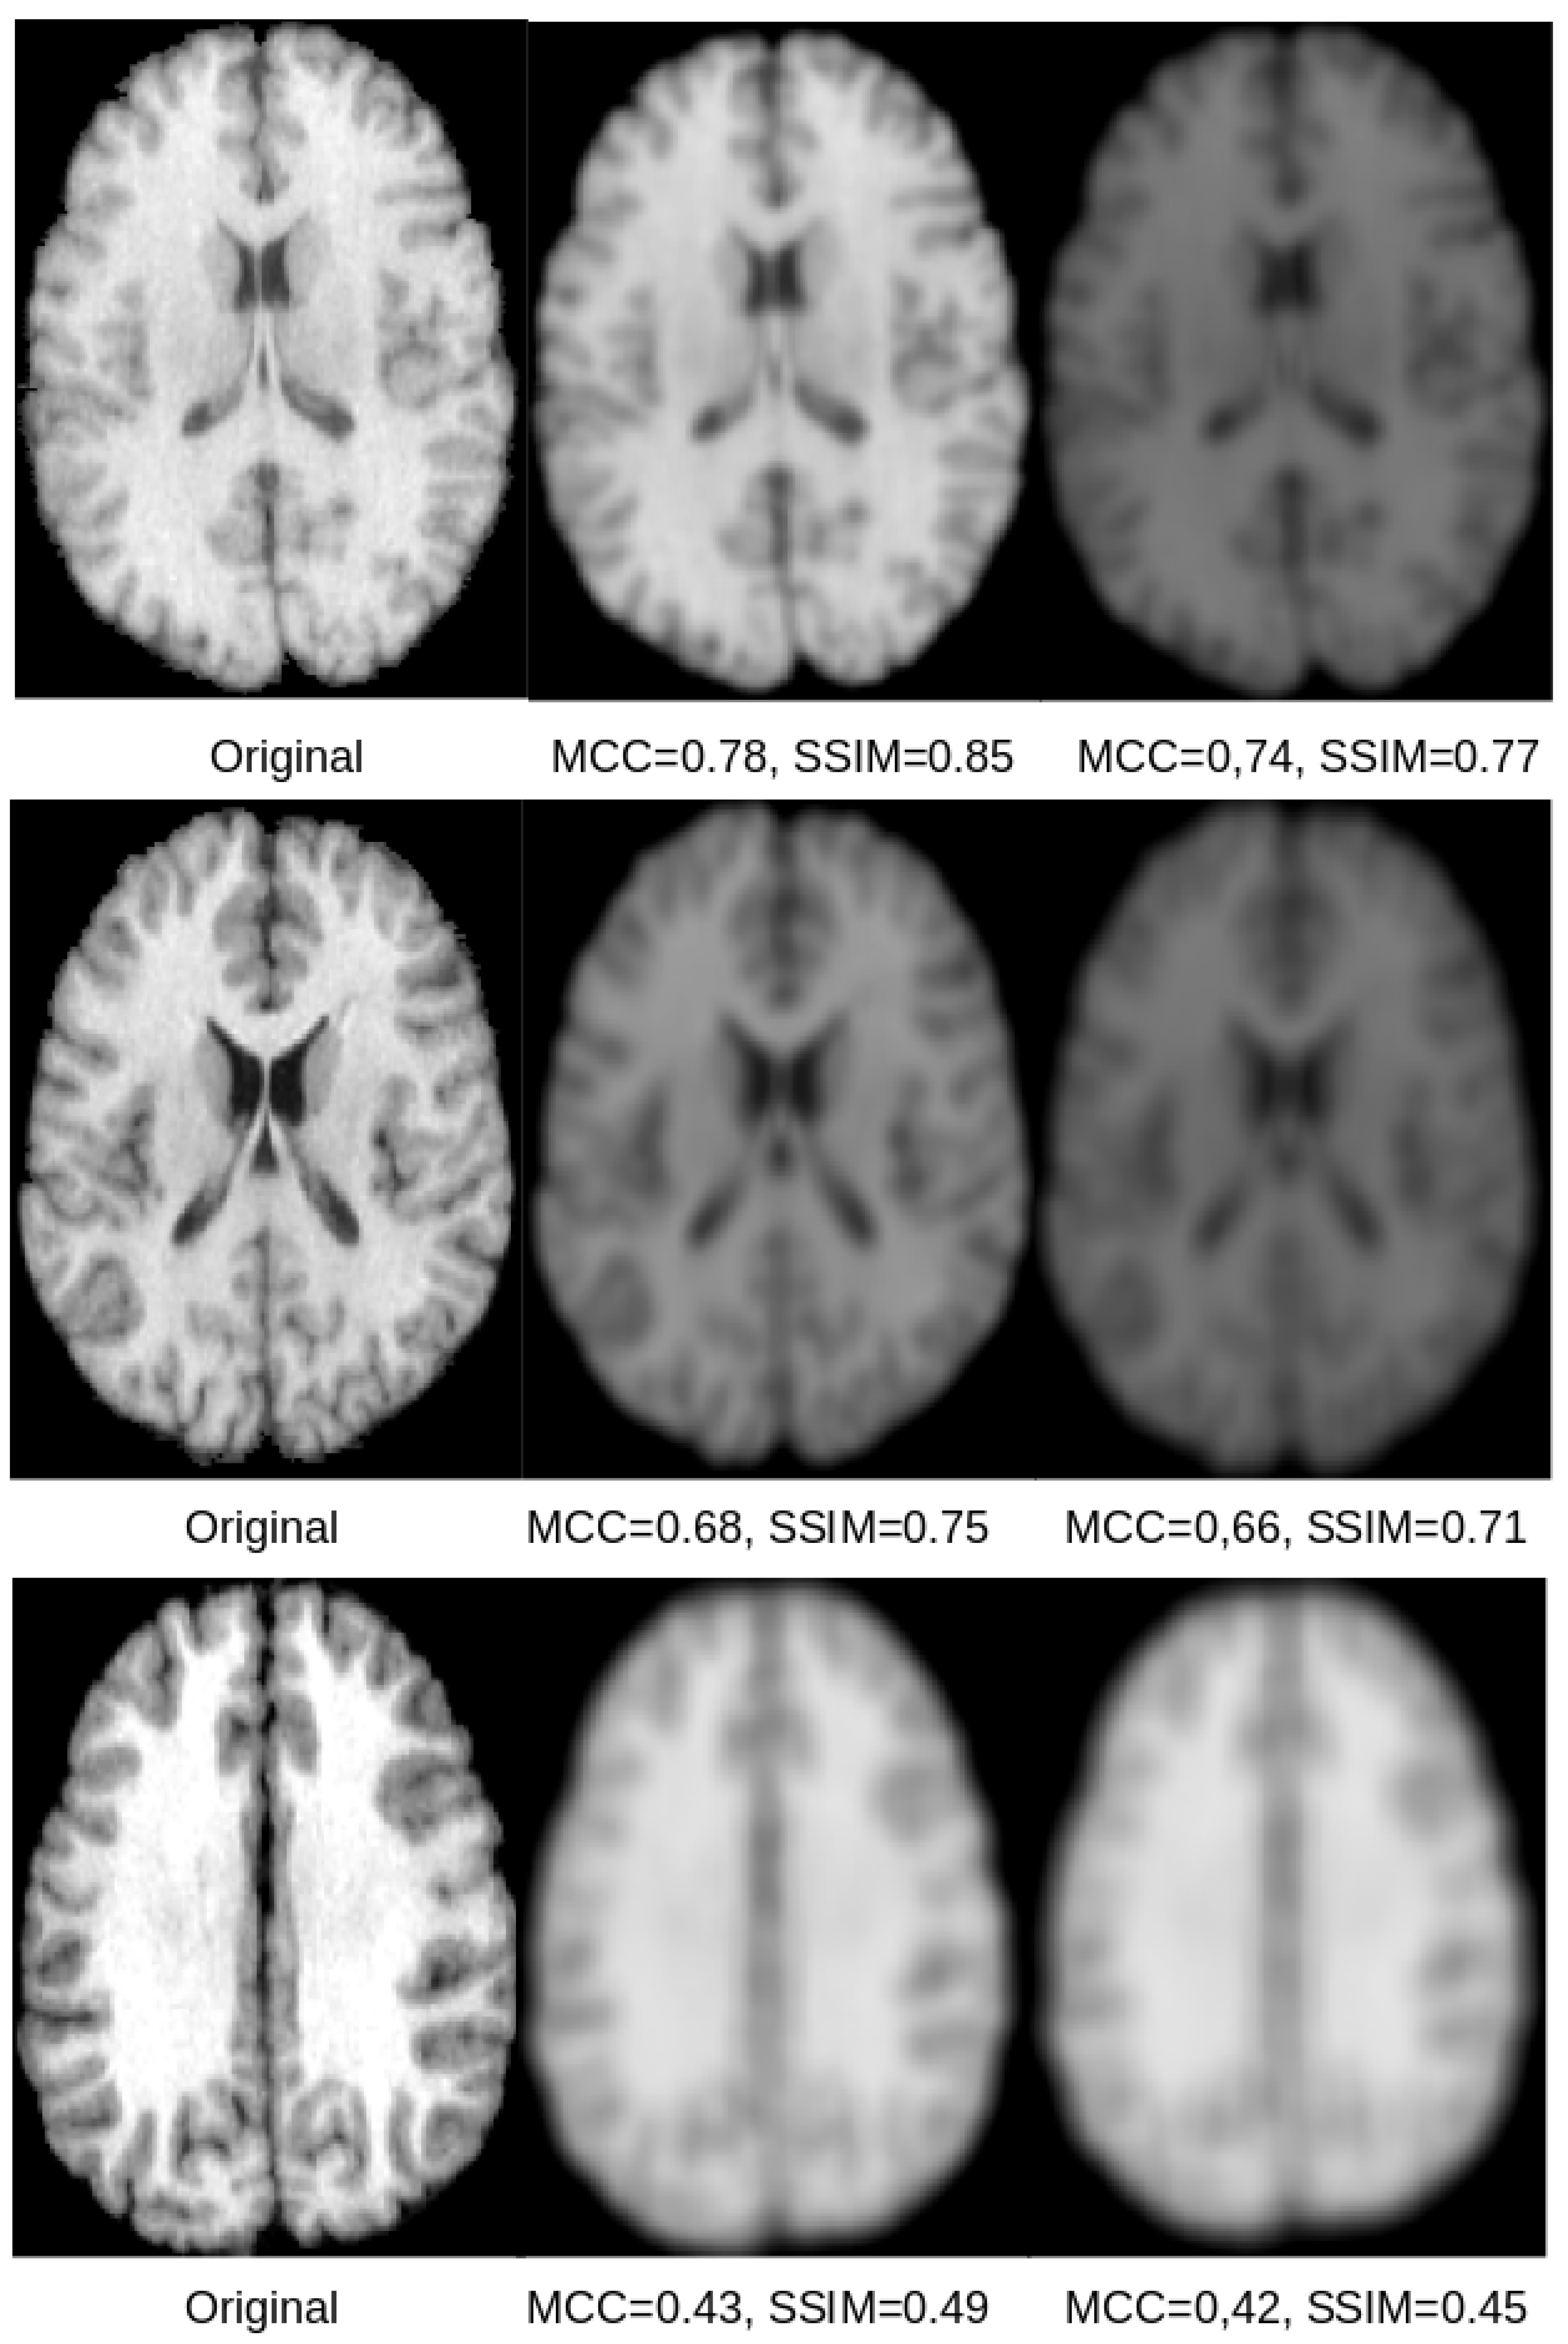

Exemplary qualitative results for U-Net and SegNet-based reconstructions for the skull-stripped and original images are shown in Figure 5 and Figure 6, respectively. Those results indicate that both SSIM and MCC in general reflect the visual quality of the reconstructed image in comparison to the original image. Both measures assign higher values to visually better reconstructions that are less blurry. However, the SSIM metric appears better suited and more sensitive to image blurring, making it the better metric for this purpose.

Figure 5.

The original skull-stripped image (left) and the corresponding reconstruction from the latent space of the U-Net (center) and SegNet (right) for three different subjects. For the subject shown in the top row, the reconstructions are sharp and there is only a scaling difference between the original and the reconstructed images. In case of the SegNet reconstruction, some minor blurring can be seen. For the subject shown in the middle row, the reconstructions show some significant degradation due to blurring, but they are still clear and recognizable. For the subject shown in the bottom row, the reconstructions show severe blurring. The corresponding SSIM and MCC scores reflect those qualitative impressions, whereas the SSIM seems generally better suited and more sensitive.

Based on the visual results exemplified in Figure 5 and Figure 6, it can be concluded that all reconstructions show some degree of blurriness. The overall reconstruction quality including the blurriness is best reflected in the SSIM scores, which range between and . Overall, the results of this study show that reconstruction of the original images used for training of CNN models is possible, but is accompanied by some amount of blurring. This finding is also in line with the results from model inversion attack studies in computer vision [8]. The results of this study also suggest that the reconstructions from the U-Net are better than those for the SegNet. A potential reason for this finding could be the skip-connections of the U-Net.